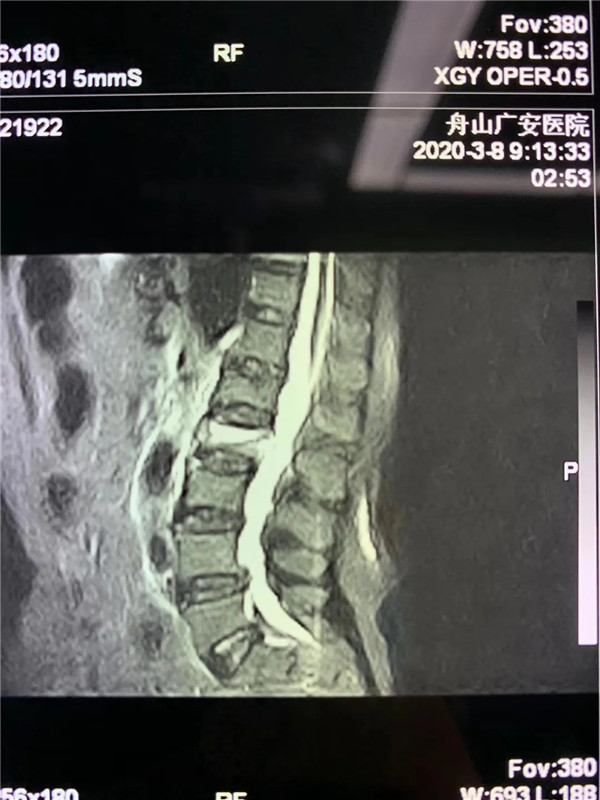

經(jīng)過(guò)仔細(xì)問(wèn)診和查體后,初步診斷曹阿姨是椎體壓縮骨折了,在完善胸腰椎的MRI線檢查后,也證實(shí)了推斷。在與曹阿姨及家屬充分溝通后,戈才華主任為曹阿姨實(shí)施了微創(chuàng)手術(shù),很快為其緩解了疼痛。

(MRI顯示椎體壓縮性骨折)